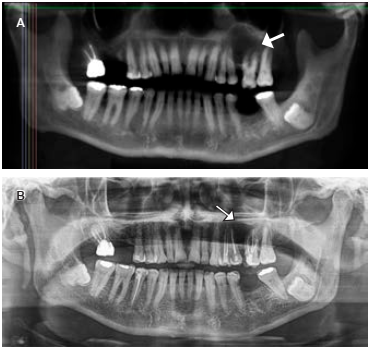

72 years old male was referred to the Facultad de Odontologia, Universidad Autónoma de Guadalajara for routine evaluation. On physical examination there was an asymptomatic patientwith preserved oral cavity, normochromic mucosa, and symmetric bone structure (Figure 1). Routine orthopantomography was requested and it demonstrated a radiolucent left maxilla region, molars and pre-molars (Figure 2). By to computed tomography (CT) with 3D reconstructionshe showedhypodense circular area (1.9 × 2.5 × 2.0 cm) with defined edges (Figure 3A) communicated with the nasal cavity, osteolysis in the palatine region and the anterior wall of the left maxilla (Figure 3B).

Figure 2 Orthopantomography. A) The arrow shows radiolucent area with a defined edge defined, B) Control orthopantomography at 6 months. The area occupied by the Keratocyst is in frank recovery.